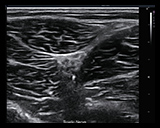

Definitive Image Quality

- A comprehensive suite of transducers cover a variety of applications and provide excellent detail, contrast resolution and image uniformity.

- Standard system configuration includes advanced image optimization technologies, including speckle reduction and spatial compounding technologies.

- High fidelity, high channel count system architecture.

- Tissue Adaptive Imaging is a unique core technology available in all imaging modes. It continuously and automatically optimizes for the anatomy being scanned to provide exceptional image quality and consistency to reduce the need for user optimization.

Ultrasound Image Application Library

Highly Flexible Across Multiple Applications

The versatile Acclarix AX8 is ideally suited for a variety of applications, procedure guidance and clinical specialties including: